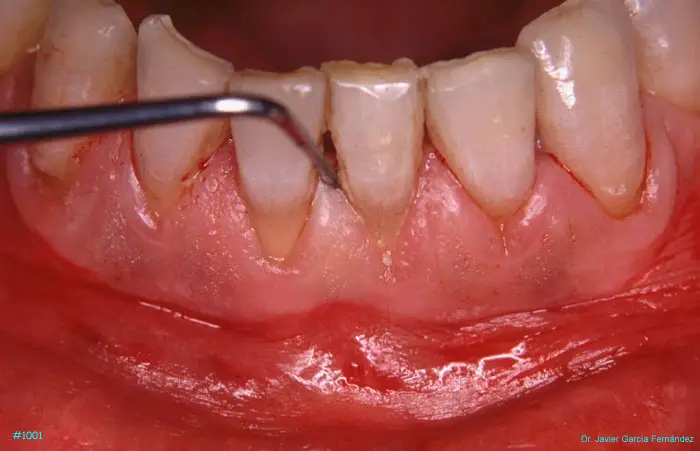

Atlas of Surgical Techniques in Periodontics. Chapter III. Atlas de Técnicas Quirúrgicas en Periodoncia